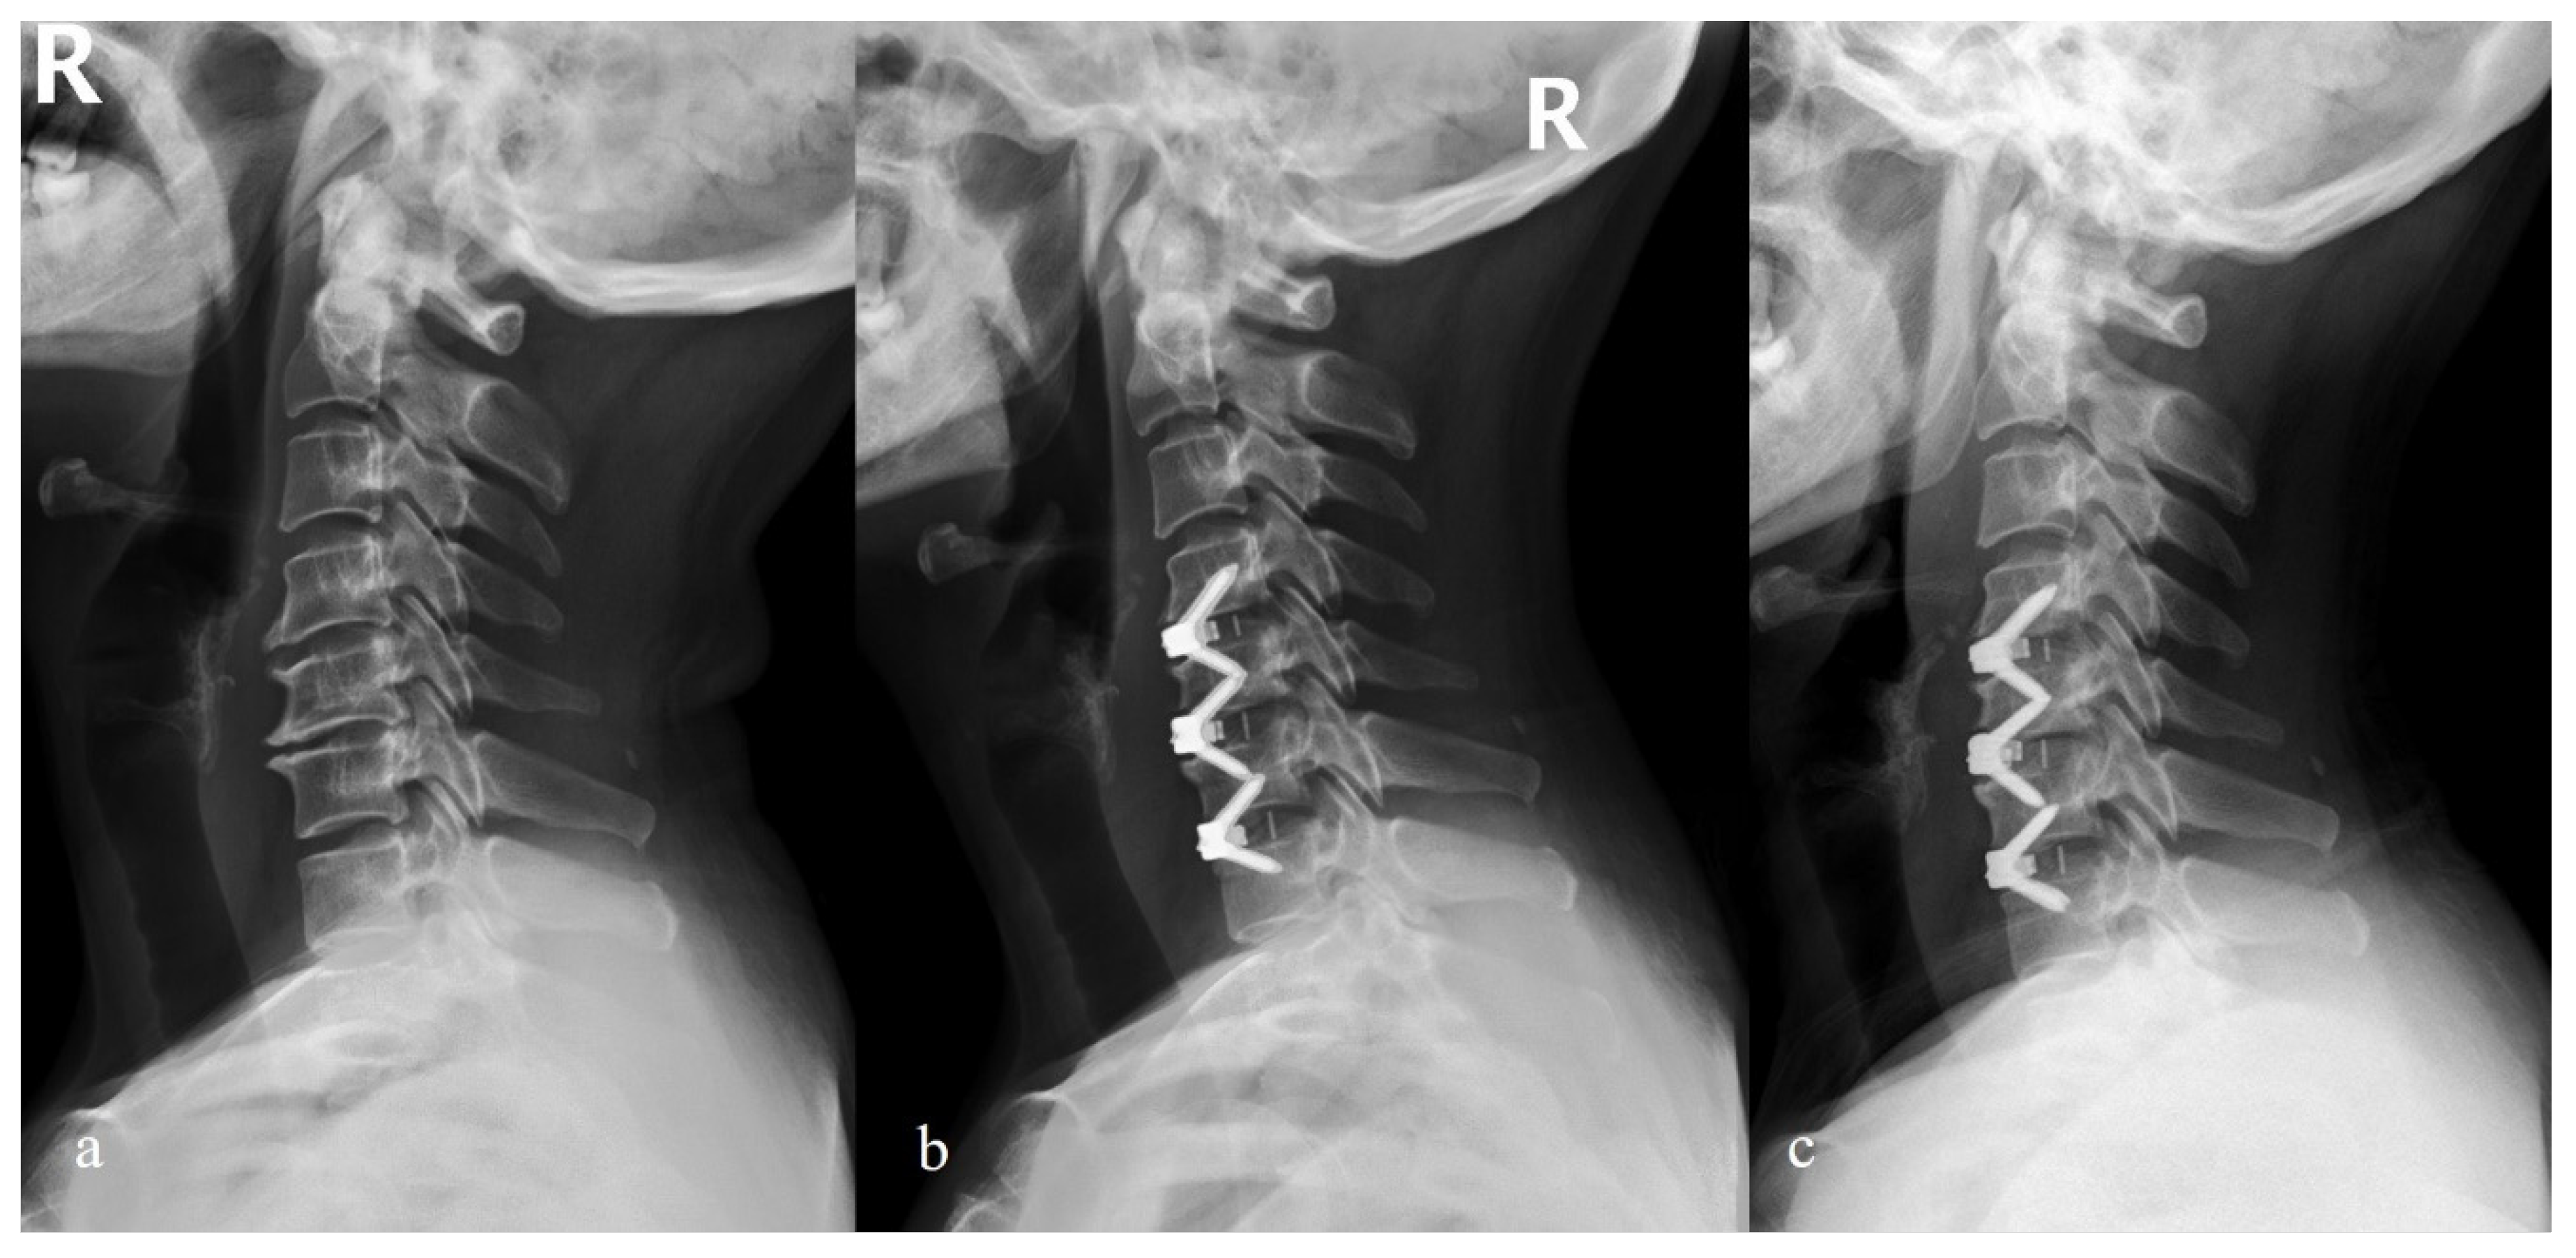

- Chen, Y.; Liu, Y.; Chen, H.; Cao, P.; Yuan, W. Comparison of Curvature Between the Zero-P Spacer and Traditional Cage and Plate After 3-Level Anterior Cervical Discectomy and Fusion: Mid-term Results. Clin. Spine Surg. 2017, 30, E1111–E1116. [Google Scholar] [CrossRef]

- Sun, B.; Shi, C.; Wu, H.; Xu, Z.; Lin, W.; Shen, X.; Wu, X.D.; Zhang, Y.; Yuan, W. Application of Zero-profile Spacer in the Treatment of Three-level Cervical Spondylotic Myelopathy: 5-year Follow-up Results. Spine 2020, 45, 504–511. [Google Scholar] [CrossRef]

- Xiao, B.; Wu, B.; Rong, T.; Cui, W.; Sang, D.; Liu, B. Clinical impact of 3-level anterior cervical decompression and fusion (ACDF) on the occipito-atlantoaxial complex: A retrospective study of patients who received a zero-profile anchored spacer versus cage-plate construct. Eur. Spine J. 2021, 30, 3656–3665. [Google Scholar] [CrossRef]